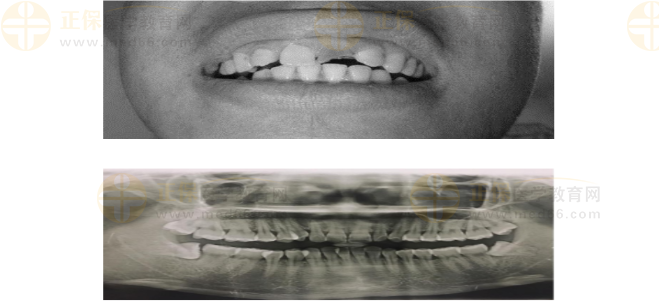

1、患者,男,38歲。上前牙變色1年,自述上前牙5年前受過(guò)外傷,唇側(cè)傾斜,檢查可見(jiàn)左上1牙冠變色,牙冠缺損近1/2,牙髓測(cè)試無(wú)反應(yīng),X線根尖片顯示患牙無(wú)明顯異常,全景片顯示雙側(cè)下頜智齒近中阻生,之前有發(fā)炎化膿病史,目前無(wú)咀嚼不適??谇黄溆酂o(wú)異常。

檢查情況及X線片見(jiàn)下圖:

(2)檢查見(jiàn)左上1牙冠變色,牙髓測(cè)試無(wú)反應(yīng),牙冠缺損近1/2,X線片無(wú)明顯異常。

非主訴疾病的診斷依據(jù):X線全景片顯示雙側(cè)下頜智齒近中阻生。